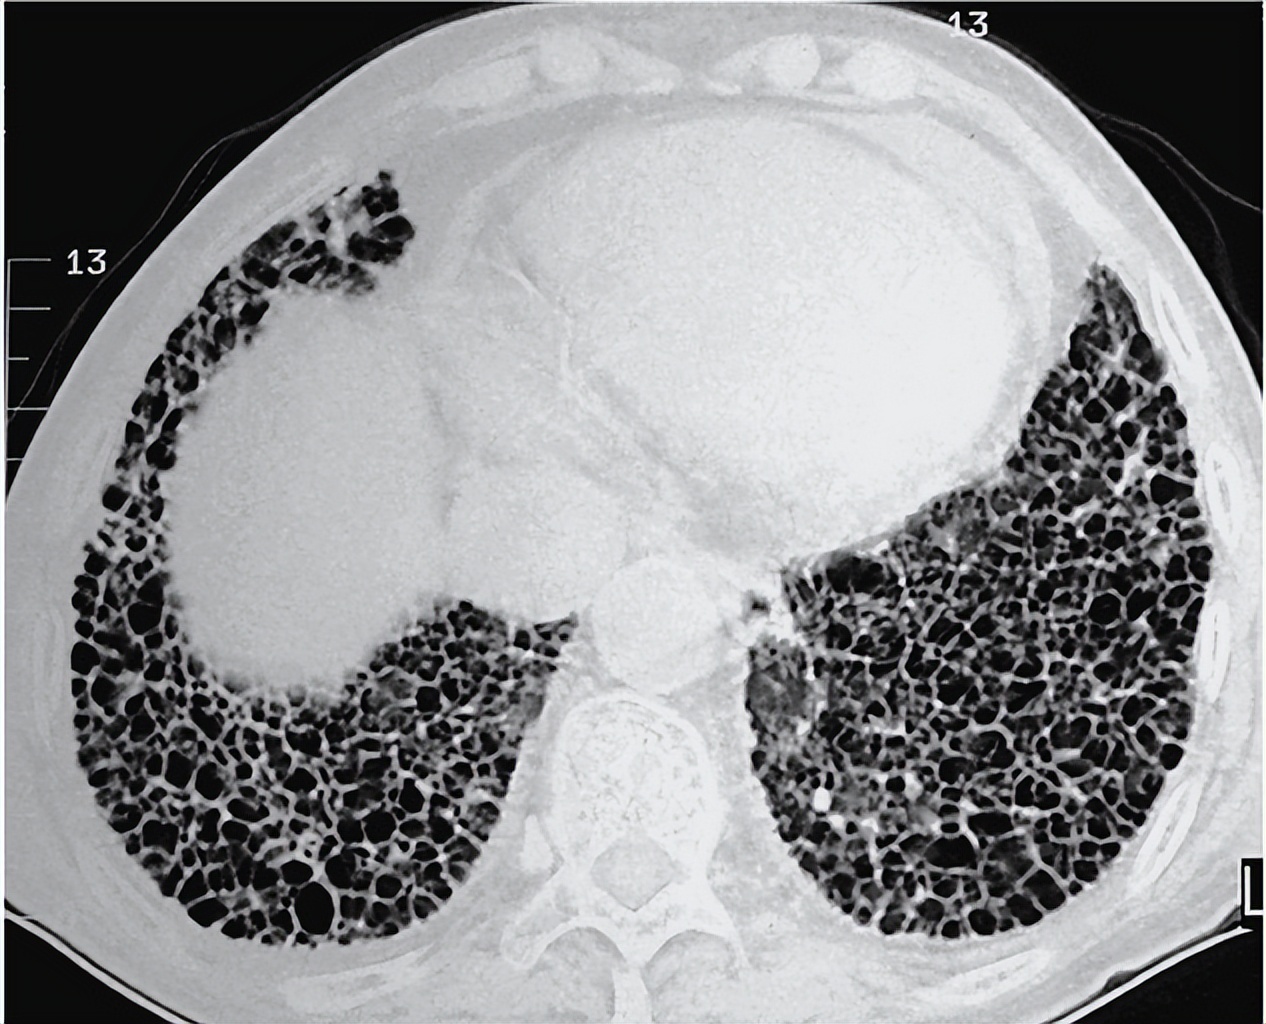

会诊我当时看的时候,他已经呼吸比较急促了,包括肾功能也不是很好,也是一个比较典型的一个百草枯临床表现

追问了病史以后,发现由于*裤内**的原因,就是*裤内**浸了百草枯以后,引起的中毒,造成的这种情况,一开始考虑浓硫酸这类的灼伤,也没有引起重视,当成普通的烧伤在治疗

张先生铃铛上的灼伤病症,医生随着治疗发现越来越不对劲,不仅伤口不见好转,甚至还出现了嗜睡、呼吸困难乃至呕吐的症状,紧急组建专家会诊,肺部异常纤维化让在座所有人百思不得其解,眼见张先生命不久矣。

他的额肺纤维化后续,有可能会有后遗症,没有完全治愈,但是目前没有生命危险